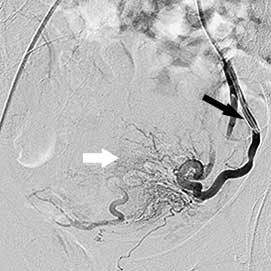

Ліва маткова артерія:

чорна стрілка - катетер, білі стрілки -

розширені артерії вузла

Після цього ендоваскулярний хірург вводить у катетер пластикові частки - емболи. Ці частинки розносяться кровотоком, і, застрягаючи в артеріях відповідного діаметра, закупорюють їх. Розмір частинок (близько 0,5 мм) спеціально підібраний таким чином, щоб вони по току крові потрапляли саме в розширені внутрішньовузлові артерії, залишаючи неушкодженими інші, менші за діаметром незмінені артеріальні гілочки. Емболізація триває до повної блокади всіх гілок, які постачають кров до вузлів, це добре видно на повторних ангіограмах.

міома матки після емболізації    міома матки після емболізації